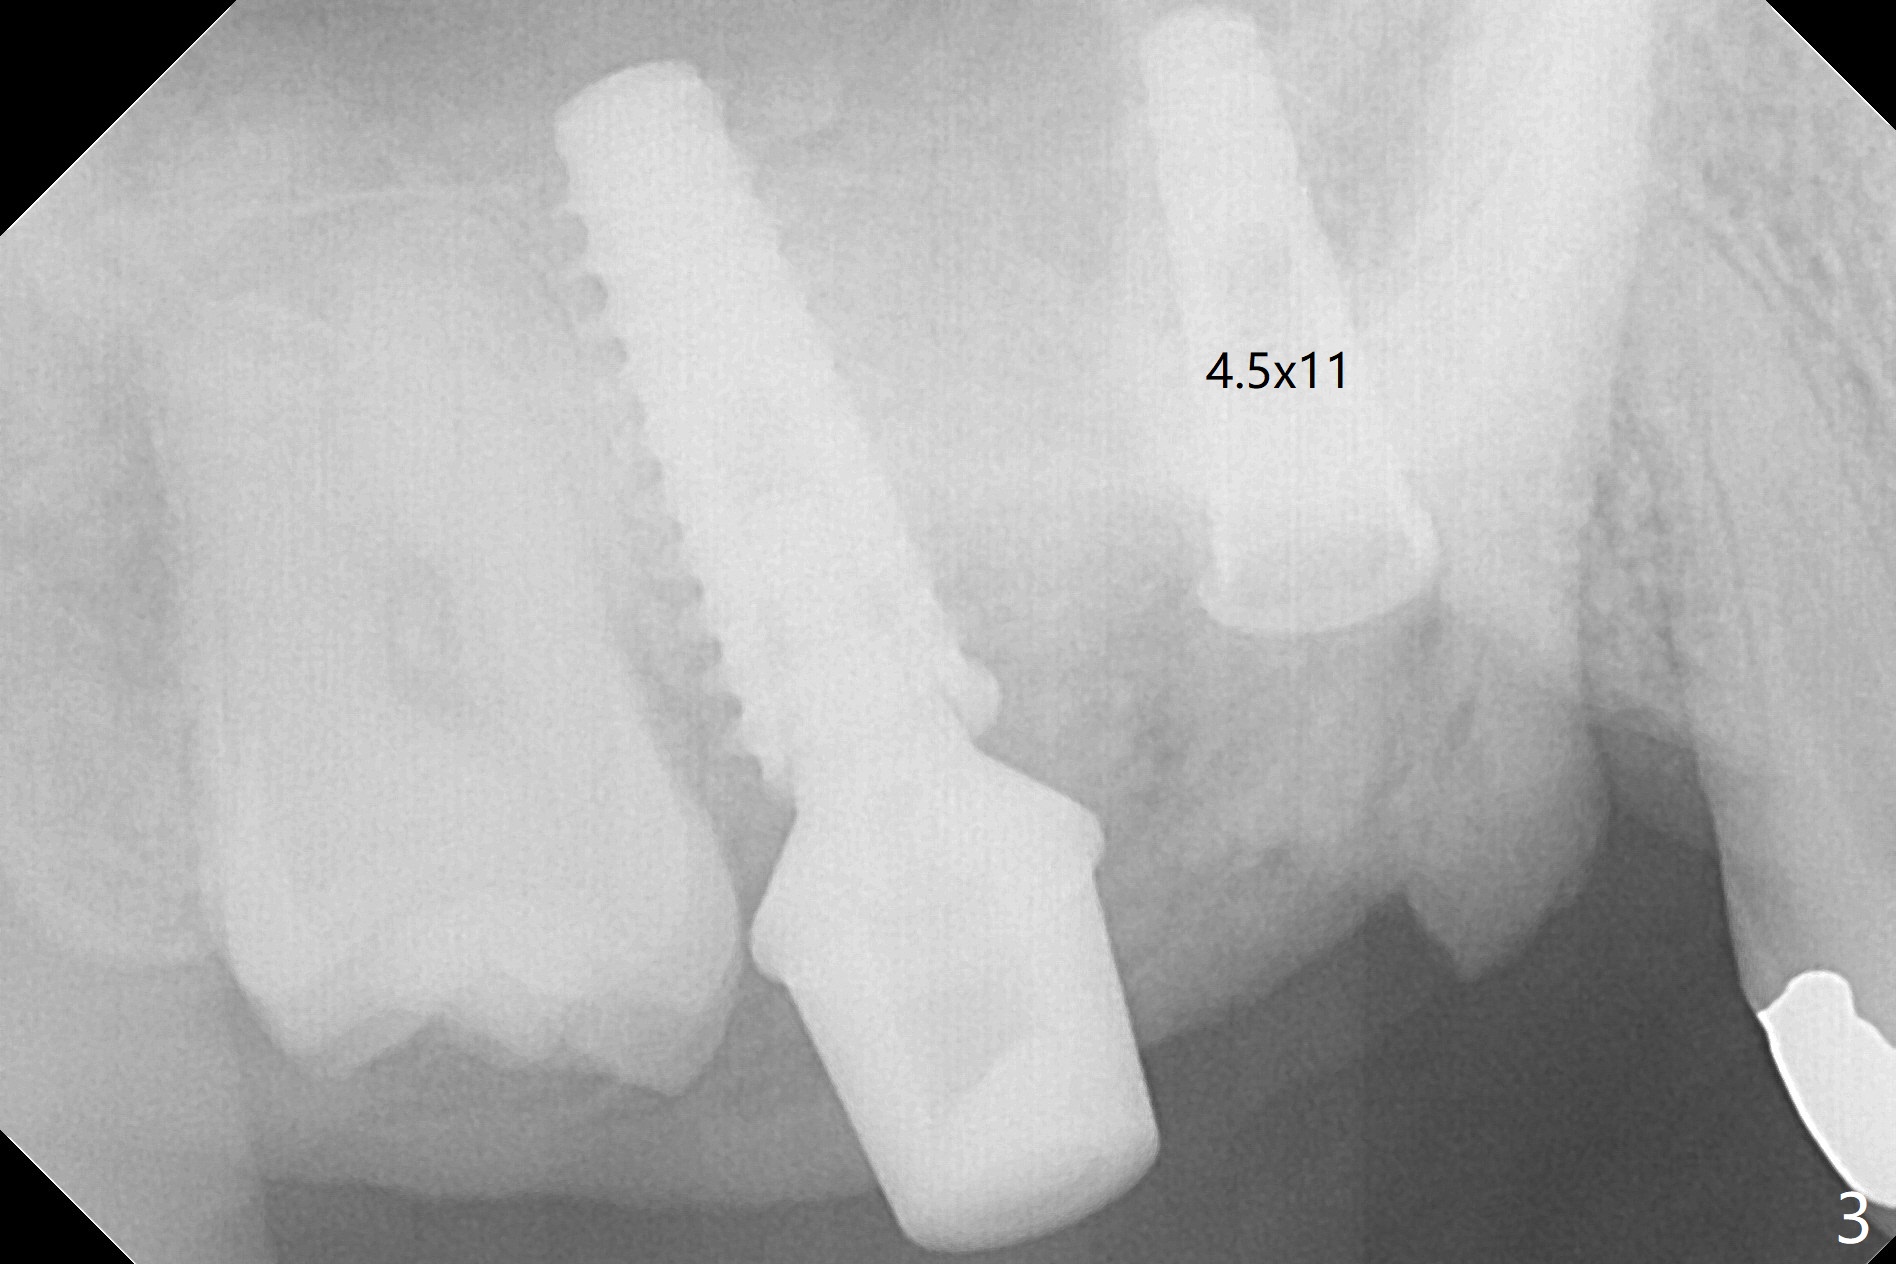

The gingiva at #2 adapts to the abutment 3.5 months post placement (Fig.1). After incision, osteotomy at #3 is initiated by free hand, which is found off (Fig.2 (red line: normal trajectory)). After repositioning osteotomy, a 4.5x11 mm dummy implant is placed with minor trajectory issue (Fig.3). Following further adjustment, a 5x11 mm implant is placed with relatively normal axis; a 6.5x4(4) mm abutment is inserted. Autogenous bone, Vanilla and Osteogen are placed distobuccally (Fig.4). Guided surgery should be more efficient and precise. There is no implant thread exposure 9 and 5 months postop at #2 and 3, respectively (Fig.5,6). The mesial wall of the crown at #2 is thin, having a crack line. The crowns at #2 and 3 are cemented with RelyX Ultimate Adhesive Resin Cement bonding. If the crown fractures, change the abutment (6.5x5.7(2) mm) to the one with smaller diameter (4.5 or 5.0 mm), or trim the abutment mesially heavily. Guided surgery or stent should prevent the potential complication.